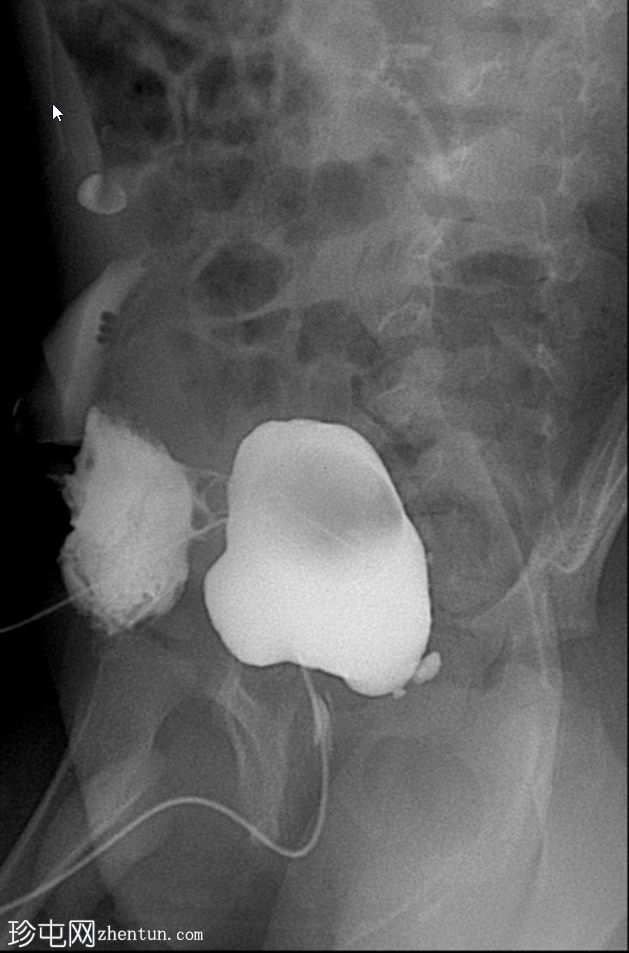

显示膀胱输尿管反流(VUR)

斜位片

使用纱布进行外部压迫成功阻塞了脐尿管开口,膀胱充盈良好。左侧输尿管和肾盂肾盏系统可见膀胱输尿管反流,符合II/III级VUR。输尿管轮廓正常,无憩室,无管壁增厚。尿道显影正常,未见后尿道瓣膜或狭窄。无肾积水。